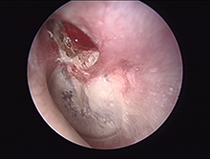

Kuppelraum- (= epitympanales) Cholesteatom mit Signalpolyp (linkes Ohr)